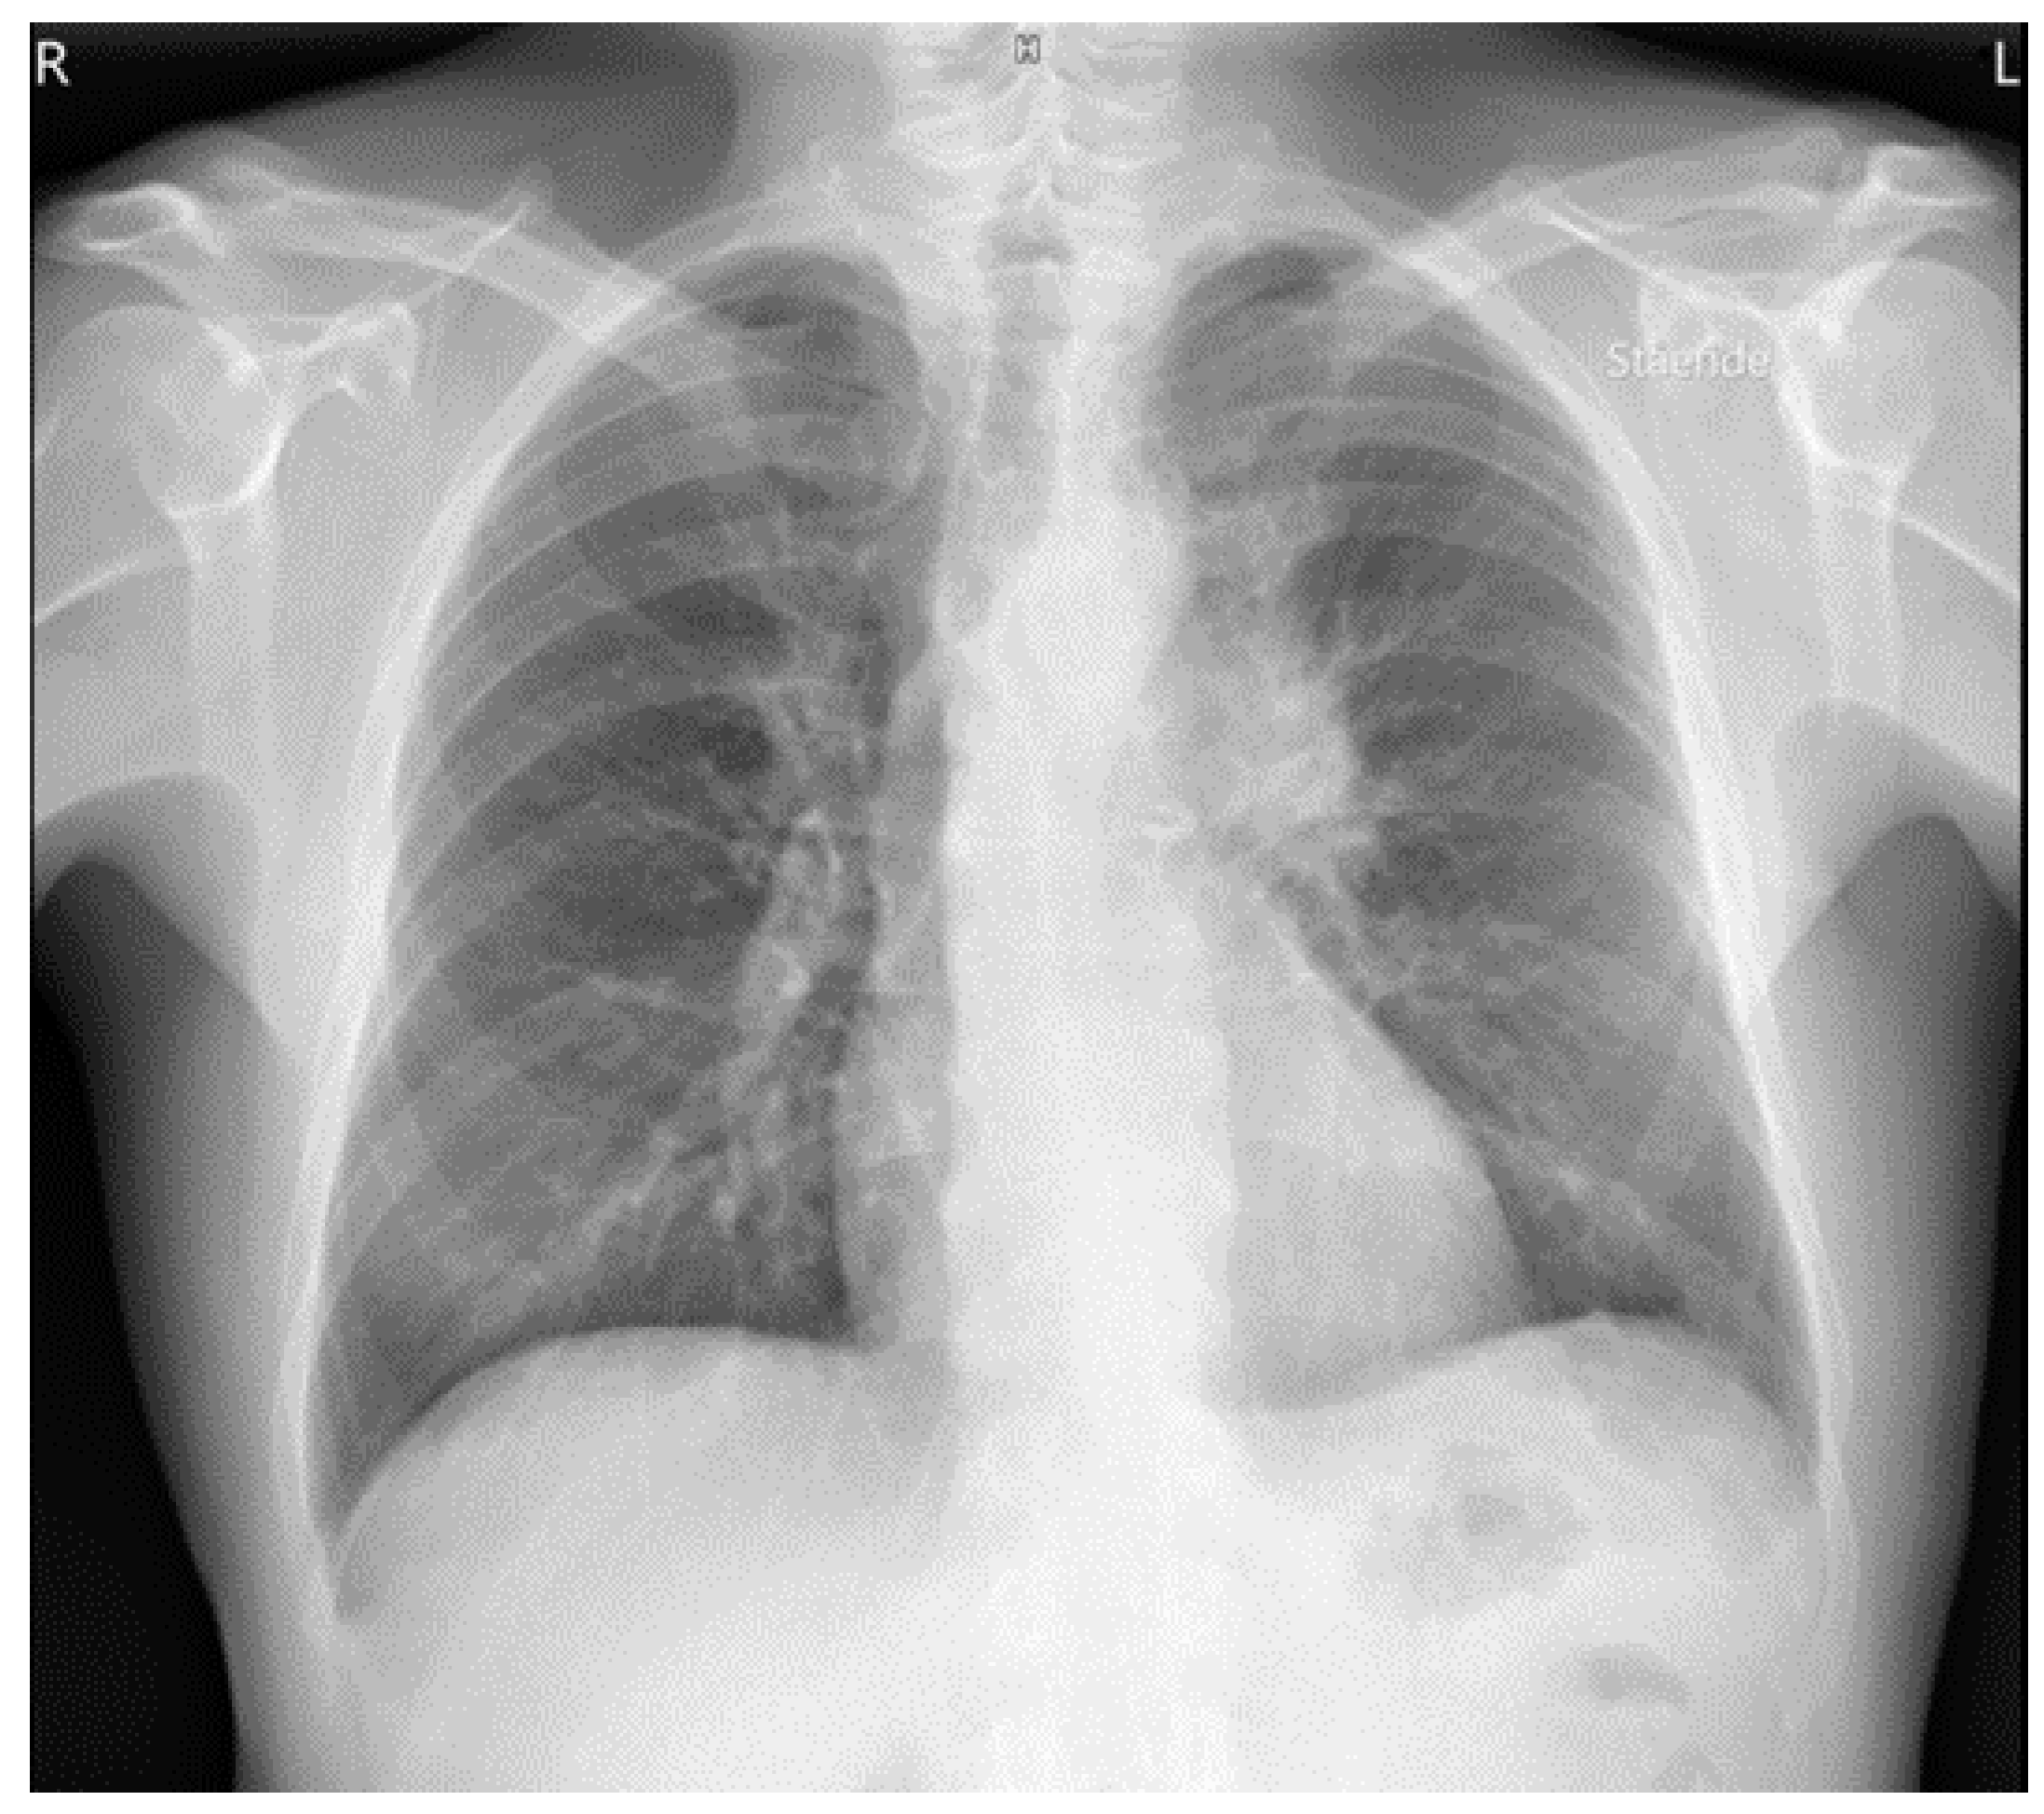

3. Results